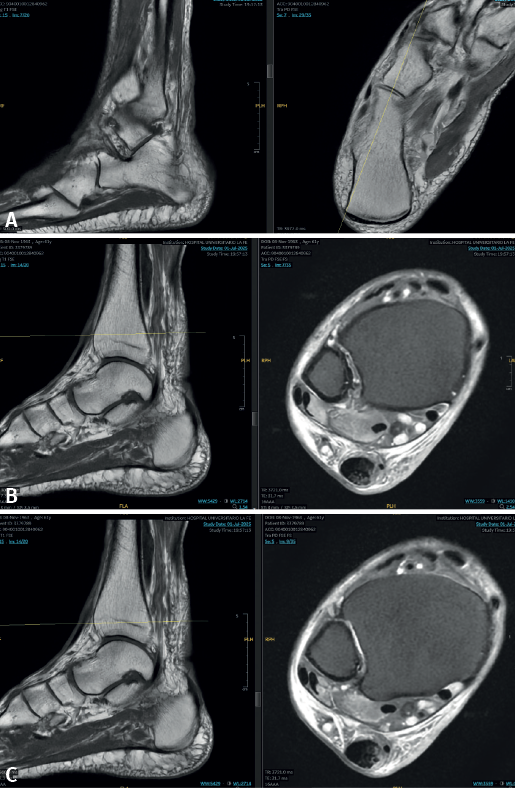

Mediante el estudio radiográfico se descartaron fracturas asociadas. Se realizó una ecografía musculoesquelética que evidenció una rotura completa del tendón TP. Se inmovilizó con un vendaje funcional y se realizó una RM que confirmó la rotura completa del tendón TP con signos de tendinopatía y con un gap de aproximadamente 10 cm (Figura 1).

Figura 1. Estudio por resonancia magnética. A: cabo distal del tendón tibial posterior (TP); B: cabo proximal del tendón TP; C: corte distal a la lesión donde se observa un vacío en el canal del TP.